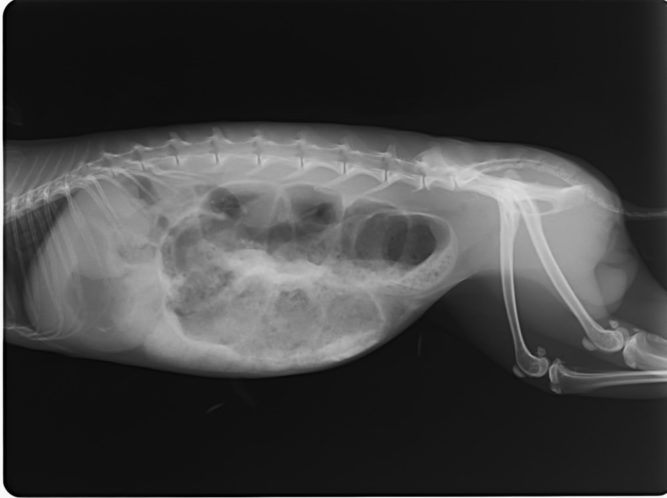

Macska allergiás dermatitis II.

Fiatal félig sziámi cica kezelése. A panaszai régóta a szemhéj szél, orrtükör sarka és szájszél pörkösödése, váladék felrakódása. Elsőként kap Imunovet, Virovet cseppet, és Cytovet 200 ml-ben higítottat itatnak napi 5 ml-t. A két hét alatt javult, a szeme és szája is szebb…